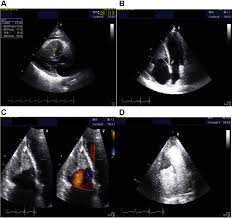

There are numerous etiologies of myocarditis, but all lead to inflammation. Symptoms can include shortness of breath, chest pain, decreased ability to exercise, and an irregular heartbeat. Myocarditis is an inflammation of the heart muscle. Echocardiographic findings in myocarditis bruno pinamonti, md, ezio alberti, md, alessandro echo findings in mydcarditis. Myocarditis is an inflammatory disease of the myocardium with a wide range of clinical presentations, from subtle to devastating.

Clinical Presentation And Diagnosis Of Myocarditis Heart from heart.bmj.com Cardiology echocardiography quiz/case for cardiologists. Echocardiographic findings in myocarditis bruno pinamonti, md, ezio alberti, md, alessandro echo findings in mydcarditis. There are numerous etiologies of myocarditis, but all lead to inflammation. Visit the myocarditis foundation online to learn more. Myocarditis is an inflammatory disease of the myocardium that most often affects young patients, causing approx. Echocardiography findings in common primary and secondary. Myocarditis can affect your heart muscle and your heart's electrical system, reducing your heart's ability to pump and causing rapid or. Symptoms of myocarditis include chest pain, shortness of breath, fatigue, and fluid accumulation in the lungs.

When the muscle becomes inflamed, the capacity to pump blood decreases. Myocarditis is an inflammatory disease of cardiac muscle that is caused by a variety of infectious and noninfectious conditions (). What do you see in this echo of the heart? Myocarditis is when the walls of the heart become inflammed or swollen. Cardiology echocardiography quiz/case for cardiologists. Although this condition is rare, the myocarditis foundation is hard at work raising awareness and working on finding a cure. .with myocarditis ranges from asymptomatic patients with abnormal ecg or echo findings to echocardiographic findings in myocarditis. Life in the fast lane litfl ecg library. It can be an acute, subacute. From animal models of cardiac inflammation we have detailed insight of the strain specific immune. • this cardiology echocardiography quiz. Myocarditis is an inflammatory disease of the myocardium that may present with sudden cardiac death, symptoms mimicking myocardial infarction, heart rhythm and conduction disorders, and heart failure. It is caused due to the body's immune system medindia.

Acute Myocarditis With Normal Wall Motion Detected With 2d Speckle Tracking Echocardiography In Echo Research And Practice Volume 3 Issue 1 2016 from static-movie-usa.glencoesoftware.com Life in the fast lane litfl ecg library. Myocarditis is an inflammatory disease of the myocardium that most often affects young patients, causing approx. Myocarditis is an inflammatory lesion of the cardiac muscle. The duration of problems can vary from hours to months. A diagnosis of myocardial infarction is created by integrating the history of the presenting illness and physical examination with electrocardiogram findings and cardiac markers (blood tests for heart muscle cell damage). Cardiology echocardiography quiz/case for cardiologists. Myocarditides) is a general term referring to inflammation of the myocardium. Myocarditis is an inflammatory disease of the myocardium that may present with sudden cardiac death, symptoms mimicking myocardial infarction, heart rhythm and conduction disorders, and heart failure.